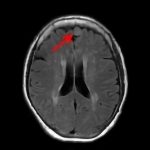

断層撮影

手術前2